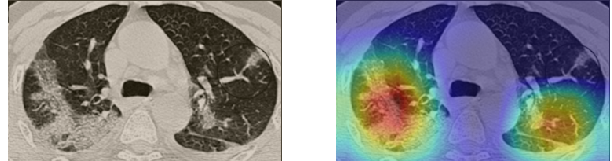

In order to make our models more transparent and provide detailed visual analysis, we present the Grad-CAM localization maps obtained by different models. We consider CT images with COVID-19 abnormalities from the test set of each dataset and highlight the important regions considered for the prediction. For the SARS-CoV-2 dataset we use the Inception V3 model. Figure 13 shows the original CT images and their localization maps. Our model is capable to detect regions that show abnormalities in the CT scans.

In a similar way, we consider classifying the test CT scans from the COVID-19 dataset by the DenseNet169 model and highlight the important regions considered for predictions. We present the original CT images and their localization maps in Figure 13. We can also see that our model is capable to detect the COVID-19 related regions as marked (small square in some images) by expert radiologists.

A wide variety of typical and atypical CT abnormalities have been reported for COVID-19 patients in various studies [58, 59]. So, we tested our models on external CT images extracted from these two publications as they feature typical findings of COVID-19 pneumonia marked by specialists. In order to make sure that not any of the extracted images are unintentionally included in our datasets, specifically the COVID19-CT dataset, we use the model trained on the SARS-CoV-2 dataset. First, the InceptionV3 model is employed to classify the extracted CT images. The model is able to correctly classify the given CT images as COVID-19. Second, in order to interpret the model’s generalization capabilities, we apply the Grad-CAM technique to visualize the regions of abnormalities that are considered. By assessing the different CT images in Figure 15, we can see that the model accurately localizes the disease-related regions. Even more interesting is the fact that the model ignores any specific marks in the images like letters and only localizes the COVID-19 related regions. These visual explanations show the success of our models to learn relevant, generic visual features related to COVID-19 and are capable to correctly classify CT images outside the datasets on which they are trained.